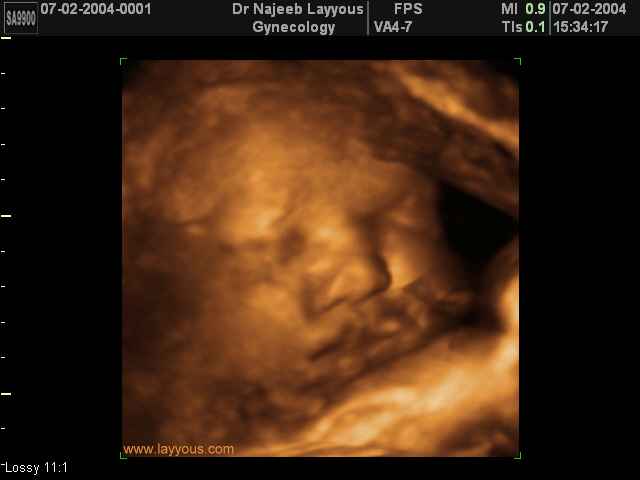

3D Fetal Face Ultrasound Scan Photos